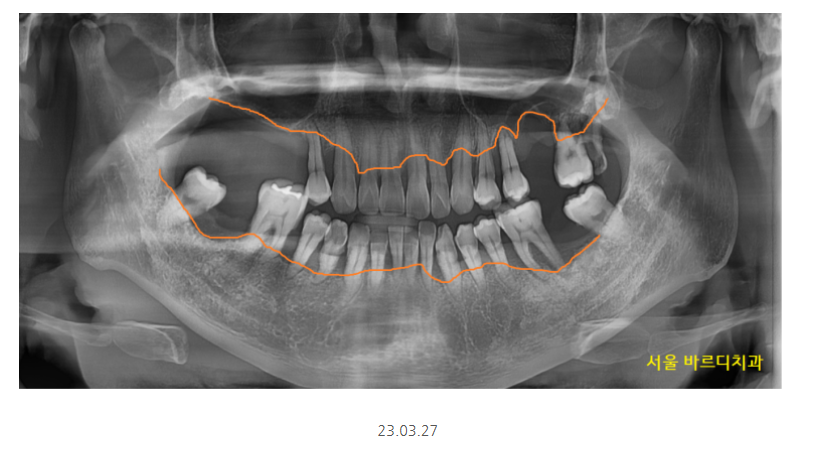

환자분처럼 양쪽 어금니가 다 없고

임플란트 뼈이식을 많이 해야할경우

안전하게 나눠서 임플란트 수술을 진행합니다.

환자분은 왼쪽이 많이 불편하시다 하셔서

1순위로 반영하여 수술해드렸는데요.

잇몸뼈가 많이 없는 상악의 경우

발치 후 뼈이식 하고 기다리다

임플란트를 심기도 하였습니다.

임플란트 뼈이식 흡연으로

충분히 기다렸습니다.

5월달에 왼쪽 위부터 수술했는데

7개월정도 지나 보철을 올려드렸어요